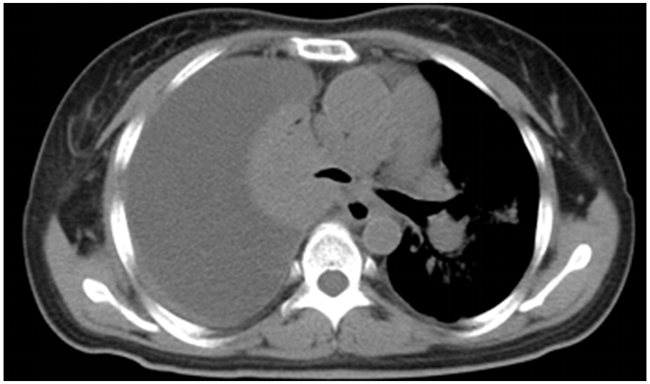

After a detailed discussion with the family and consent of the mother and sister, the patient was administrated with EGFR TKI- gefitinib at a dose of 250 mg once a day for the first-line treatment. The symptom, such as cough and short of breath both relieved after one week. Two months later, CT scan showed shrinked all of the primary and metastatic tumors and decreased pleural effusion. The principal complications of this regimen were 1 grade diarrhea and rash. A repeat CT scan after six months of therapy was performed due to worsening short of breath. The radiological findings consisted of increase in size of both of the primary tumor as well as liver mass and pleural effusion but not new metastases (Figure 2). The best response of the first-line treatment is stable disease according to Response Evaluation Criteria In Solid Tumors (RECIST version 1.0), and the progression-free survival was six months.

Figure 2: Six months after treated with Gefitinib, a repeat CT scan showed the disease progressed.